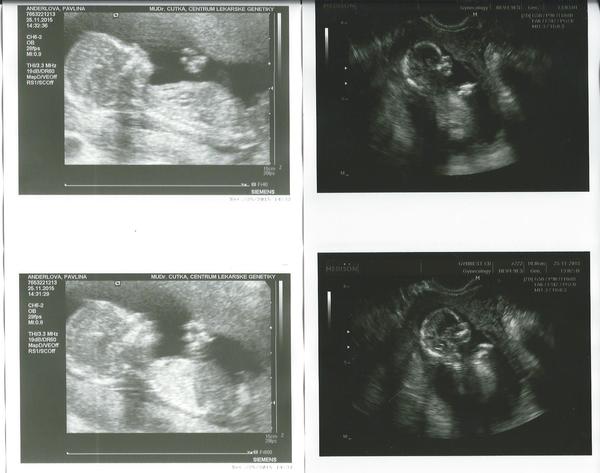

@briketaaaa krásná fotecka😊

@briketaaaa krásna foto 🙂..,gratuluji už ted je nádherný 😉

@briketaaaa Ten je krásný😊vypada moooc spokojene,nam udelaji 4D az po 20tt u dvojčátek😊